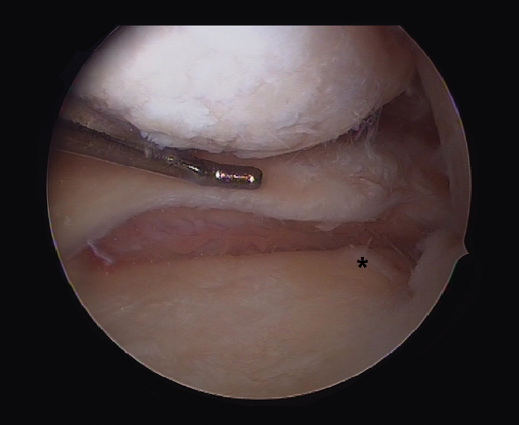

Although recently greater importance is being placed on the presence of so-called meniscal ramp lesions (Figure 3), with an estimated incidence of up to 23.9%(19) associated to ACL rupture, these lesions were already described by Strobel(20) in 1988 as a particular type of meniscal injury associated to ACL rupture and affecting the peripheral insertion of the posterior horn of the medial meniscus. These injuries are also referred to as hidden lesions of the posterior horn of the medial meniscus, since they may go undetected in the MRI studies(21). From the biomechanical perspective, ramp lesions of the knee with ACL rupture increase anterior translation of the tibia, internal and external rotation, and pivot shift. If not repaired, rotational stability following reconstruction of the ligament likewise is not fully restored(22).

Figure 3. Repair of a lesion of the posterior ramp of the medial meniscus (*) adopting a posteromedial arthroscopic approach. Trans-notch view from the anterolateral port. Working cannula in the posteromedial port (PMP). IFC: internal femoral condyle. Right knee.